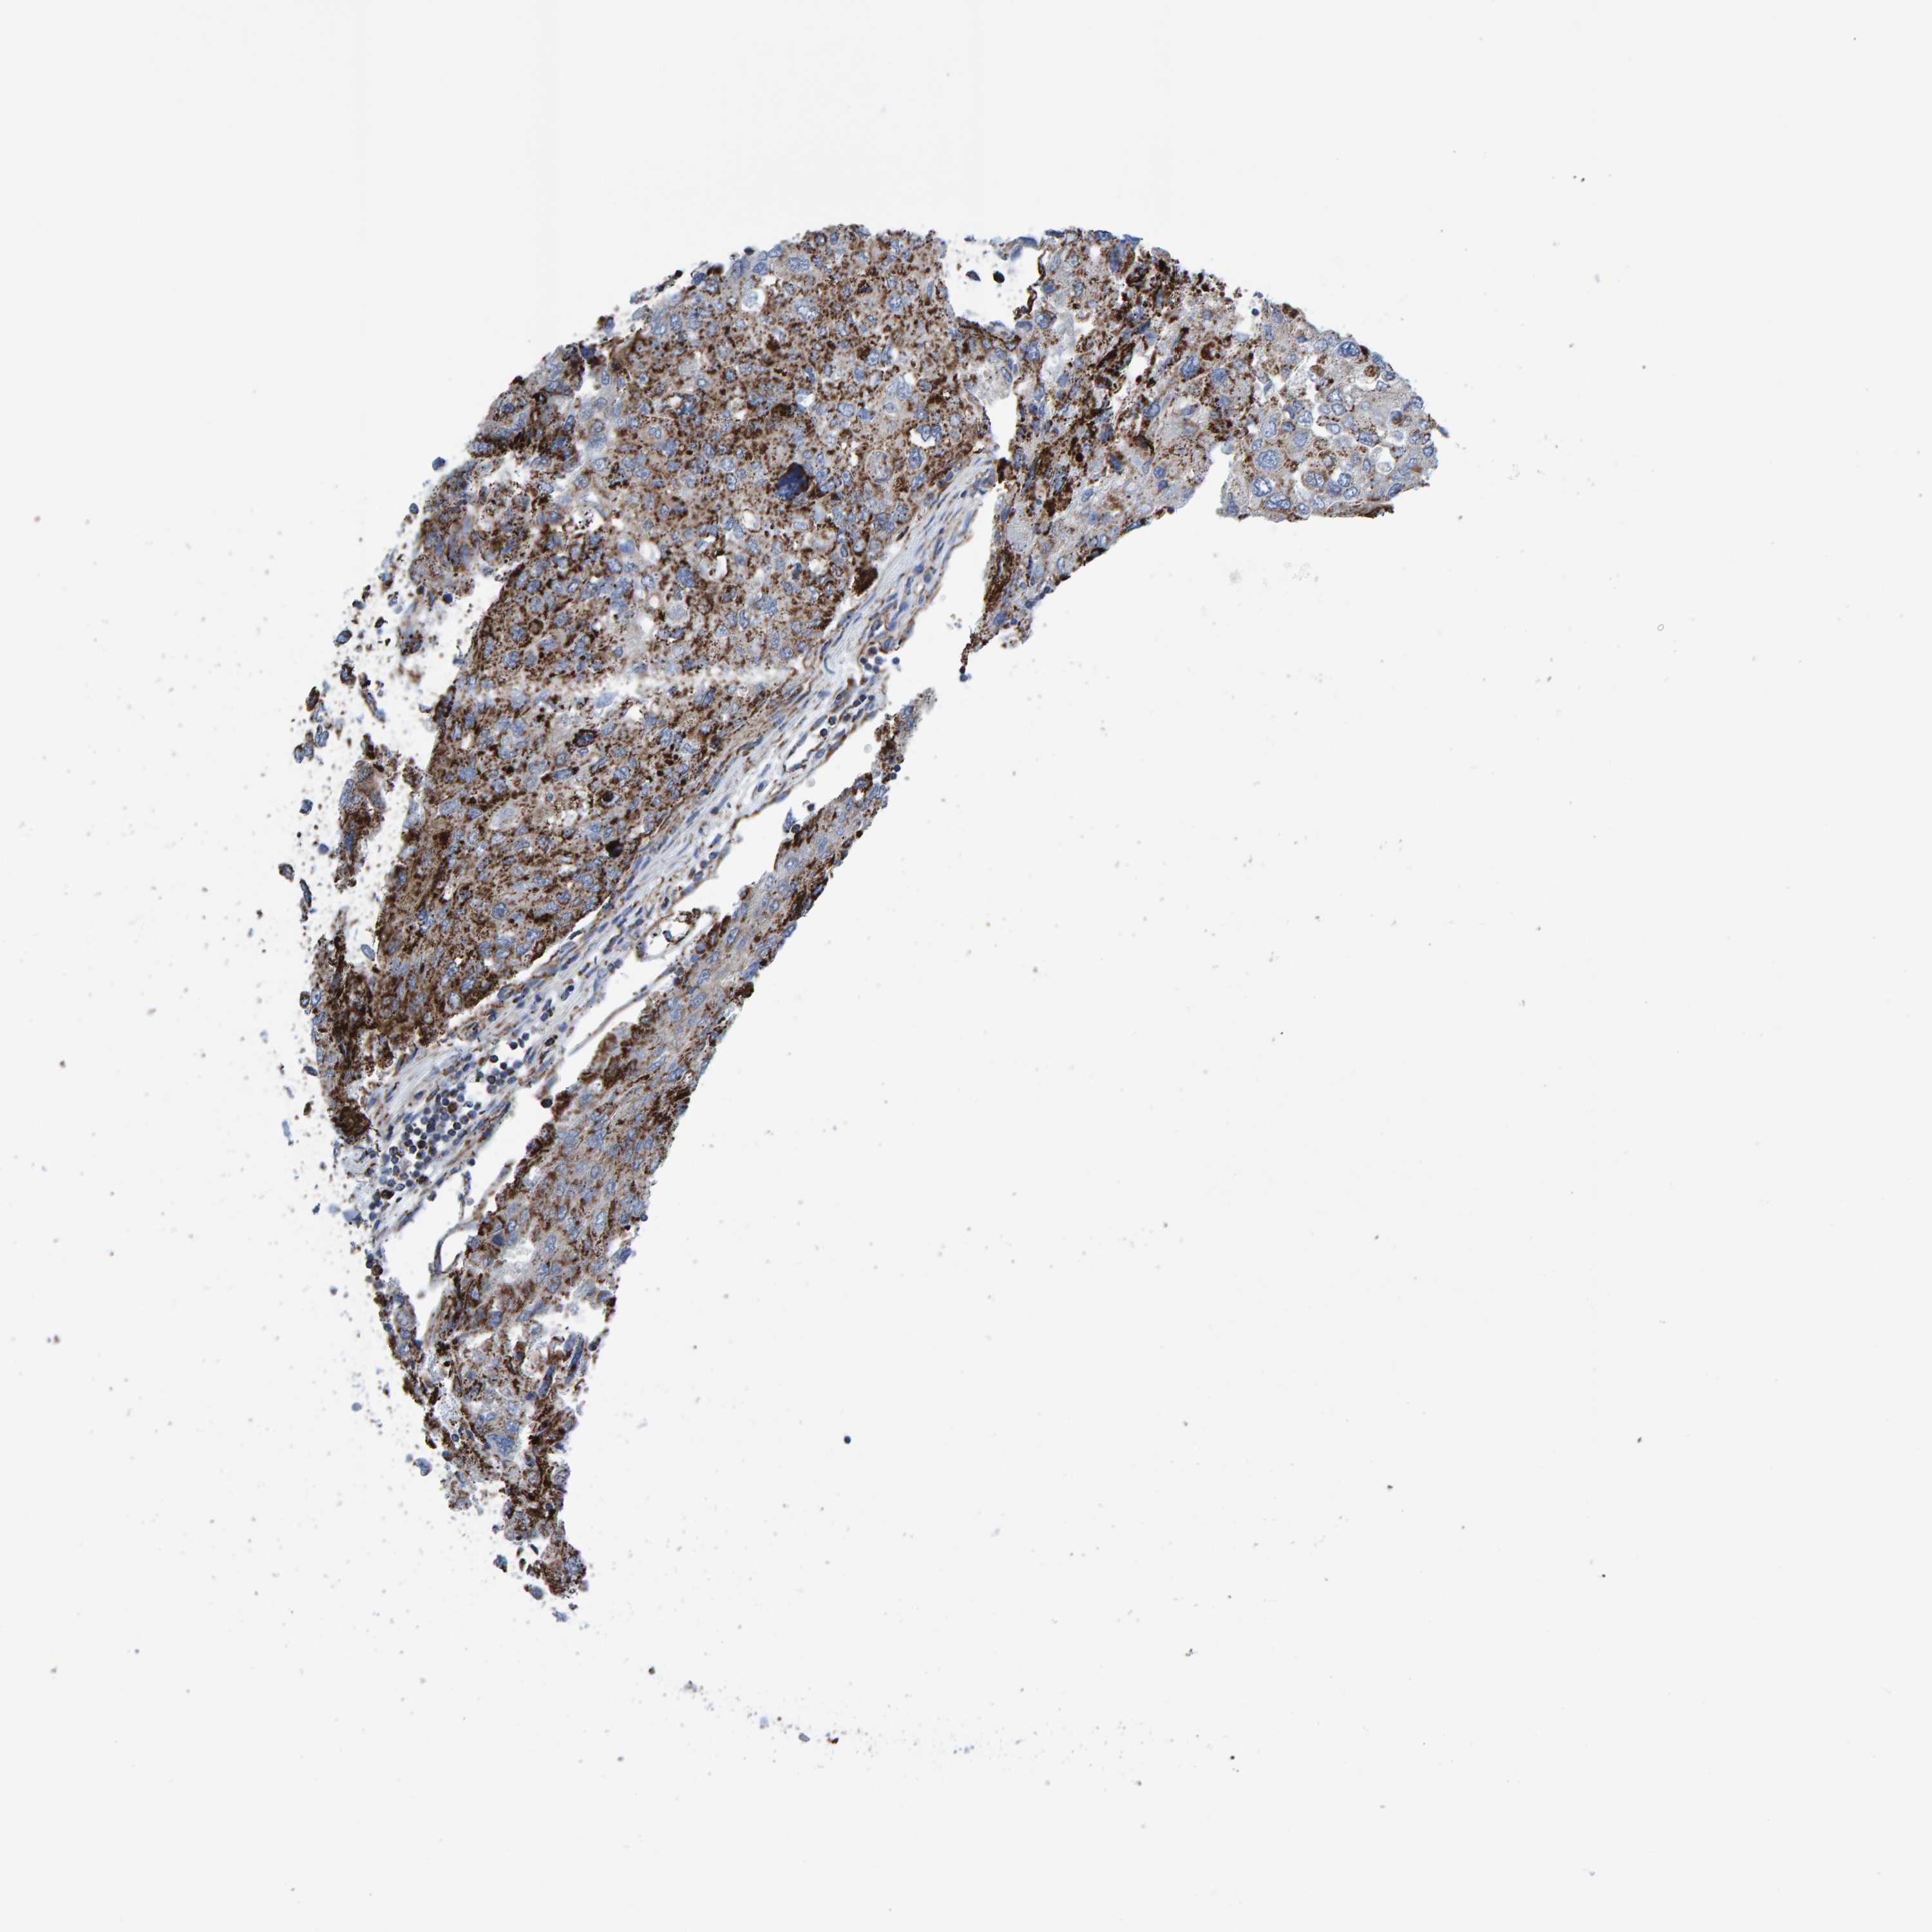

UROTHELIAL CANCER - Protein expressioni

A mouse-over function shows sample information and annotation data. Click on an image to view it in a full screen mode. Samples can be filtered based on level of antibody staining by selecting one or several of the following categories: high, medium, low and not detected. The assay and annotation is described here.

Note that samples used for immunohistochemistry by the Human Protein Atlas do not correspond to samples in the TCGA dataset.

Antibody stainingi

Antibody staining in the annotated cell types in the current human tissue is reported as not detected, low, medium, or high, based on conventional immunohistochemistry profiling in selected tissues. This score is based on the combination of the staining intensity and fraction of stained cells.

Each image is clickable and will lead to virtual microscopy that enables deeper exploration of all samples and also displays staining intensity scores, fraction scores and subcellular localization as well as patient and tissue information for each sample.

Antibody HPA022853

Antibody HPA023043

Antibody HPA023048

Staining

High

Medium

Low

Not detected

Intensity

Strong

Moderate

Weak

Negative

Quantity

>75%

75%-25%

<25%

None

Location

Nuclear

Cytoplasmic/membranous

Cytoplasmic/membranous,nuclear

Urothelial carcinoma, Low grade

Urothelial carcinoma, High grade